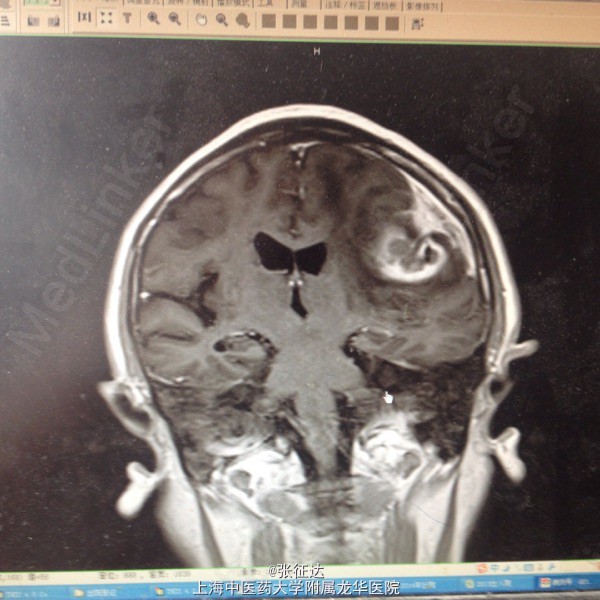

神情,GCS14分,右侧肢体肌力III级,病理症(-)。头颅CT:左侧顶叶区占位

复查头颅MR表现为左侧顶叶占位。择期全麻下行手术治疗后取病理,提示脑脓肿